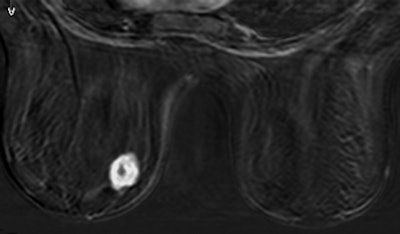

| Thirty-two-year-old woman with ductal infiltrating adenocarcinoma measuring 18 mm in maximum transverse diameter. Axial fused PET/CT images obtained with patient in prone position at time point 1 (above) and time point 2 (below) show corresponding standard uptake values. |

![]() |